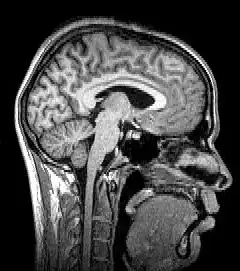

Median plane sagittal tomography of the head by magnetic resonance imaging

Tomography is imaging by sections or sectioning that uses any kind of penetrating wave. The method is used in radiology, archaeology, biology, atmospheric science, geophysics, oceanography, plasma physics, materials science, cosmochemistry, astrophysics, quantum information, and other areas of science. The word tomography is derived from Ancient Greek τόμος tomos, "slice, section" and γράφω graphō, "to write" or, in this context as well, "to describe." A device used in tomography is called a tomograph, while the image produced is a tomogram.